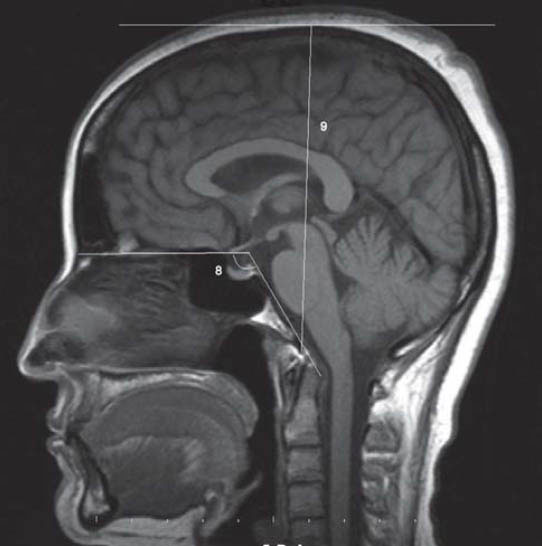

Cranium dimensions differ according to racial, geopraphic, ethnic and nutritional factors. This study will shed light on the question “Is there a difference in the cranial distances measured between congenital bilateral blind people and healthy individuals?” Nine anthropometric measures were performed on the brain MRI midsagittally obtained from male and female congenital bilateral blinds. The anthropometric measures taken included the glabella-opisthocranion, nasion-dorsum sellae, dorsum sellae-opisthocranion, nasion-basion, nasion-opisthion, basion-opisthion, prosthion-basion, basion-vertex and the clival angle. In addition, the supratentorial and infratentorial areas were calculated. Glabella-opisthocranion, nasion-dorsum sellae, nasion-basion, prosthion-basion and clival angle were found to be smaller in the congenital bilateral blind females compared to the healthy group, but these results were not statistically significant. Whereas, other measures out of the basion-opisthion were found to be smaller in the congenital bilateral blind males than in the healthy subjects. Of these results, the distance between glabella-opisthocranion, nasion-dorsum sellae and nasion-basion was significantly smaller compared to the measurements taken from the healthy male group. The infratentorial area was significantly smaller in congenital blind male subjects and the supratentorial area was significantly larger in congenital blind female subjects. This study has revealed that the cranium dimensions of congenital blind people are to different from normal individuals. The most significant difference was in the distance of the nasion-dorsum sellae. The region anterior to the basion and dorsum sellae was prominently smaller. The infratentorial area was significantly smaller in congenital blind male subjects and the supratentorial area was significantly larger in congenital blind female subjects.